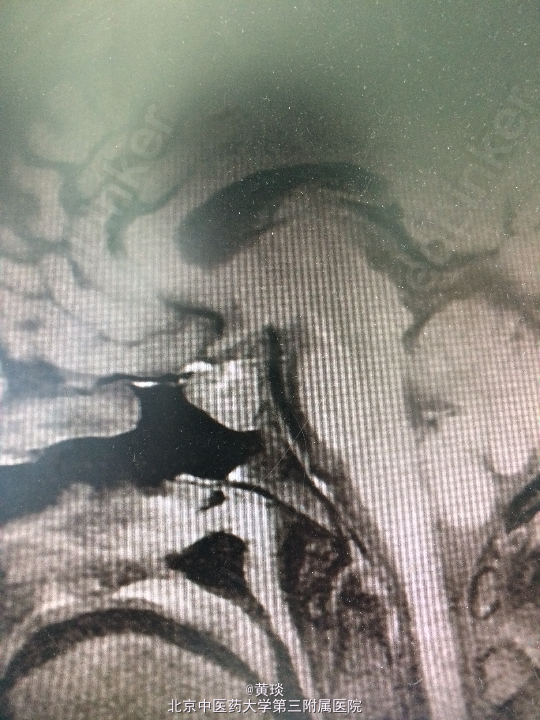

患者女,49岁,主诉:间断头痛2年,视物模糊1年。 现病史:患者2年前无明显诱因出现头痛,为前额钝痛,症状间断出现,发作时无恶心呕吐、无肢体抽搐、无肢体无力及大小便障碍、无意识障碍,未进行系统诊治。一年前起患者自觉视物模糊,偶伴有发热及烦躁不安,无面部感觉异常及眼球活动受限,无闭经泌乳、无多饮及多尿,右耳偶有耳鸣,无听力下降,无发作性头晕及走路不稳,无饮水呛咳及声音嘶哑,门诊行头部MRI检查,提示鞍上异常信号影。以“鞍区占位”收入院。

查体:双侧瞳孔等大等圆,直径约2mm,对光反射灵敏,左侧视力0.5,右侧视力0.6。其余无异常。 门诊头部MRI:提示鞍上异常信号影。

诊断:鞍区占位 处理:全麻下行经鼻蝶鞍区占位切除术

术前考虑的诊断:1.垂体瘤:为鞍区最常见肿瘤,患者可伴或不伴内分泌症状,临床可表现为视力视野受损或内分泌改变如多饮多尿等,影像学检查可见鞍区占位性病变,依据患者症状体征及辅助检查,诊断可能性大,具体待术后病理。 2.鞍区脑膜瘤:为鞍区常见肿瘤,多分布于蛛网膜颗粒聚集处,边界清楚,均匀强化,有时可见脑膜尾征,临床可表现为颅内占位效应,如视力下降等,依据患者症状体征及辅助检查,该诊断不能排除,具体待术后病理。 3.鞍区动脉瘤:较少见,但手术风险大,临床表现为视力改变,影像学见占位边界清楚,MRI见血管流空影,该诊断可能性小,但不能排除。 4.颅咽管瘤:多发于鞍区,儿童多见,临床可表现为视力下降或内分泌改变,影像学检查就CT可见蛋壳样钙化,该诊断基本可排除。 术后病理确诊为垂体瘤。